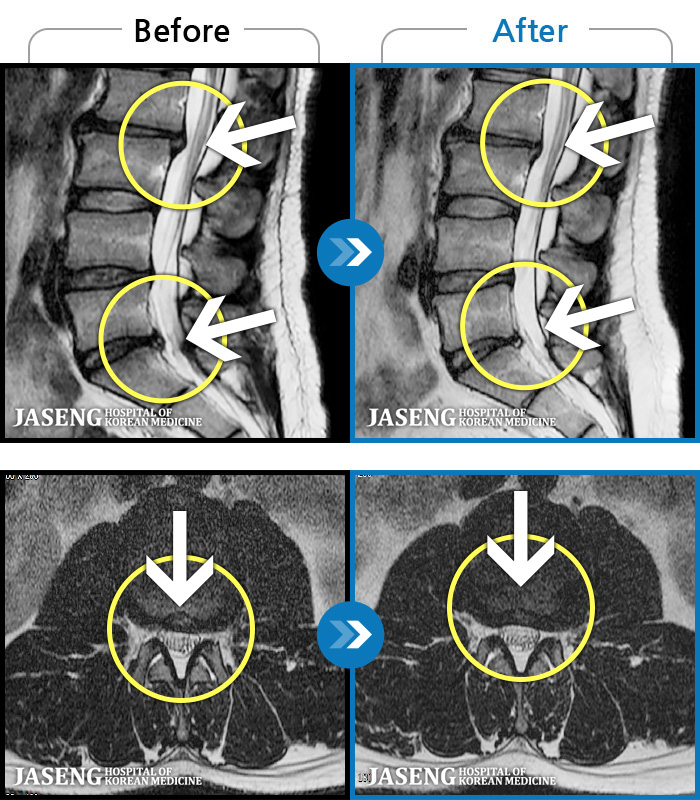

MRI ġ

1,245 MRI ũ ʸ Ȯϼ.